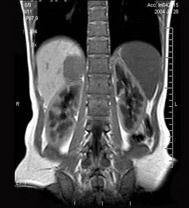

问题 男,31岁,体检时超声发现右肾上腺区病灶,MRI扫描如图所示,下列说法正确的是()

选项 A.右侧肾上腺区可见一类圆形病灶,与周围组织分界清楚 B.该病灶在T1WI为等信号,在T2WI为稍高信号 C.考虑为右侧肾上腺腺瘤 D.考虑为右侧肾上腺髓样脂肪瘤 E.考虑为右侧肾上腺嗜铬细胞瘤

答案 ABC